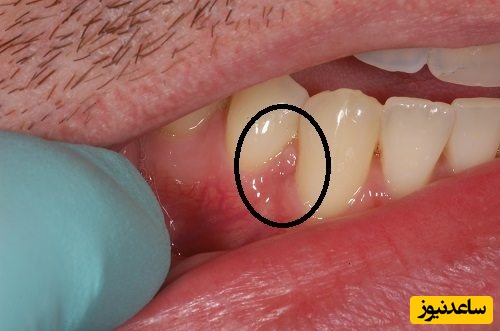

عفونتی که کاملا باکتریایی است. و ناشی از پوسیدگی های شدید و عفونت دندان روی لثه ها ایجاد می شود، را در علم دندان پزشکی کیست دندان می گویند.افرادی که دچار التهابات لثه ای هستند، معمولا درگیر این بیماری می شوند. اما فقط 10 درصد از آنها متوجه این بیماری شده و برای درمان کیست دندان اقدام می کنند. کیست دندان در صورتی که درمان نشود می تواند استخوان فک و لثه را درگیر کرده و موجب ایجاد کیست های لثه ای شود.

این نوع کیست شایعترین نوع کیست دهان و دندان است که با نام های مختلفی چون کیست پریودنتال، کیست دندان و یا کیست ریشه معروف است. علت بروز این کیست از بین رفتن پالپ های موجود دررون دندان است. پالپ ها بر اثر پوسیدگی و یا ضایعه های دندانی از بین می رود. درمان این کیست معمولاً با روش ENDO صورت می گیرد. در این روش متخصص با روش های جراحی به انتهای عصب فرد دسترسی پیدا می کند تا کیست و یا عفونت را بردارد. در برخی مواقع درمان ENDO تاثیر گذار نیست و متخصص مجبور به کشیدن دندان می شود تا محل کیست را تمیز کند سپس با مواد مصنوعی آن ناحیه را پر می کند.

این کیست بیشتر در اطراف دندان های نیش بالا و عقل پایین و در اطراف تاج دندان ایجاد می شود. علت به وجود آمدن کیست دنتیجروس، فشاری است که بر روی فولیکول وارد می شود. این فشار وارده باعث ایجاد اختلال در جریان خون و تجمع مایع میان بافت غشای مینای دندان می شود. کیست فولیکولار به سرعت رشد می کند به همین دلیل به محض مشاهده باید به متخصص مراجعه شود.در درمان کیست دنتیجروس و یا فولیکولار ناحیه آسیب دیده را برداشته و کیست را جراحی می کنند در بیشتر مواقع این نوع درمان موفقیت آمیز است.